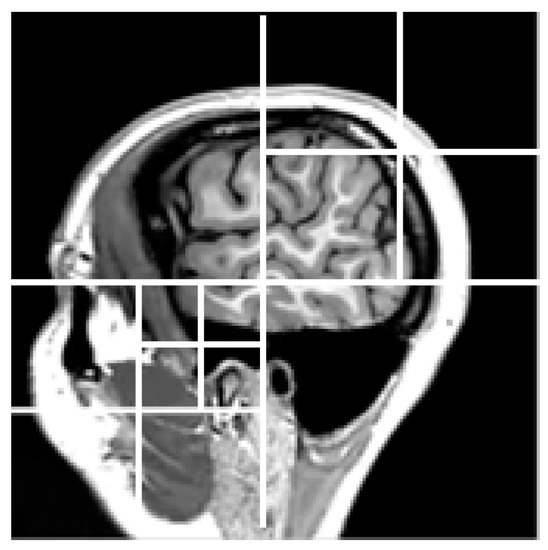

Second, to construct a bandelet basis on the whole wavelet domain, we use a quadtree segmentation at each wavelet scale in dyadic squares, as shown in Figure 3 where the main steps for computing bandelet transform are summarized and illustrated on a brain magnetic resonance image (MRI). Note that we define a different quadtree for each scale of the wavelet transform (in Figure 3 only the quadtree of the finest scale is depicted). More specifically, we use the same quadtree for each of the three orientations of the wavelet transform at fixed scale.

Figure 3.

Example of graphical steps of the bandelet transformation algorithm illustrated on a brain magnetic resonance image (MRI) (T2-weighted image acquired at 3 T).